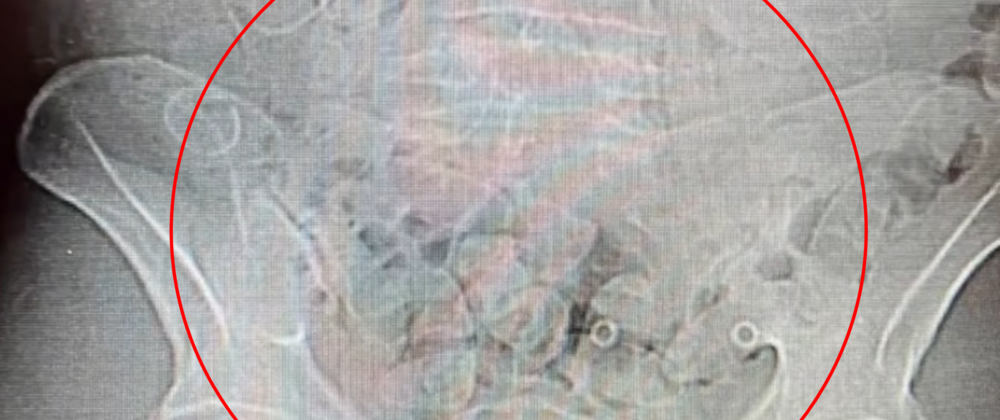

40-letni mężczyzna został przewieziony do szpitala, gdzie wykonano badanie tomografem komputerowym, które potwierdziło obecność narkotyków w organizmie.